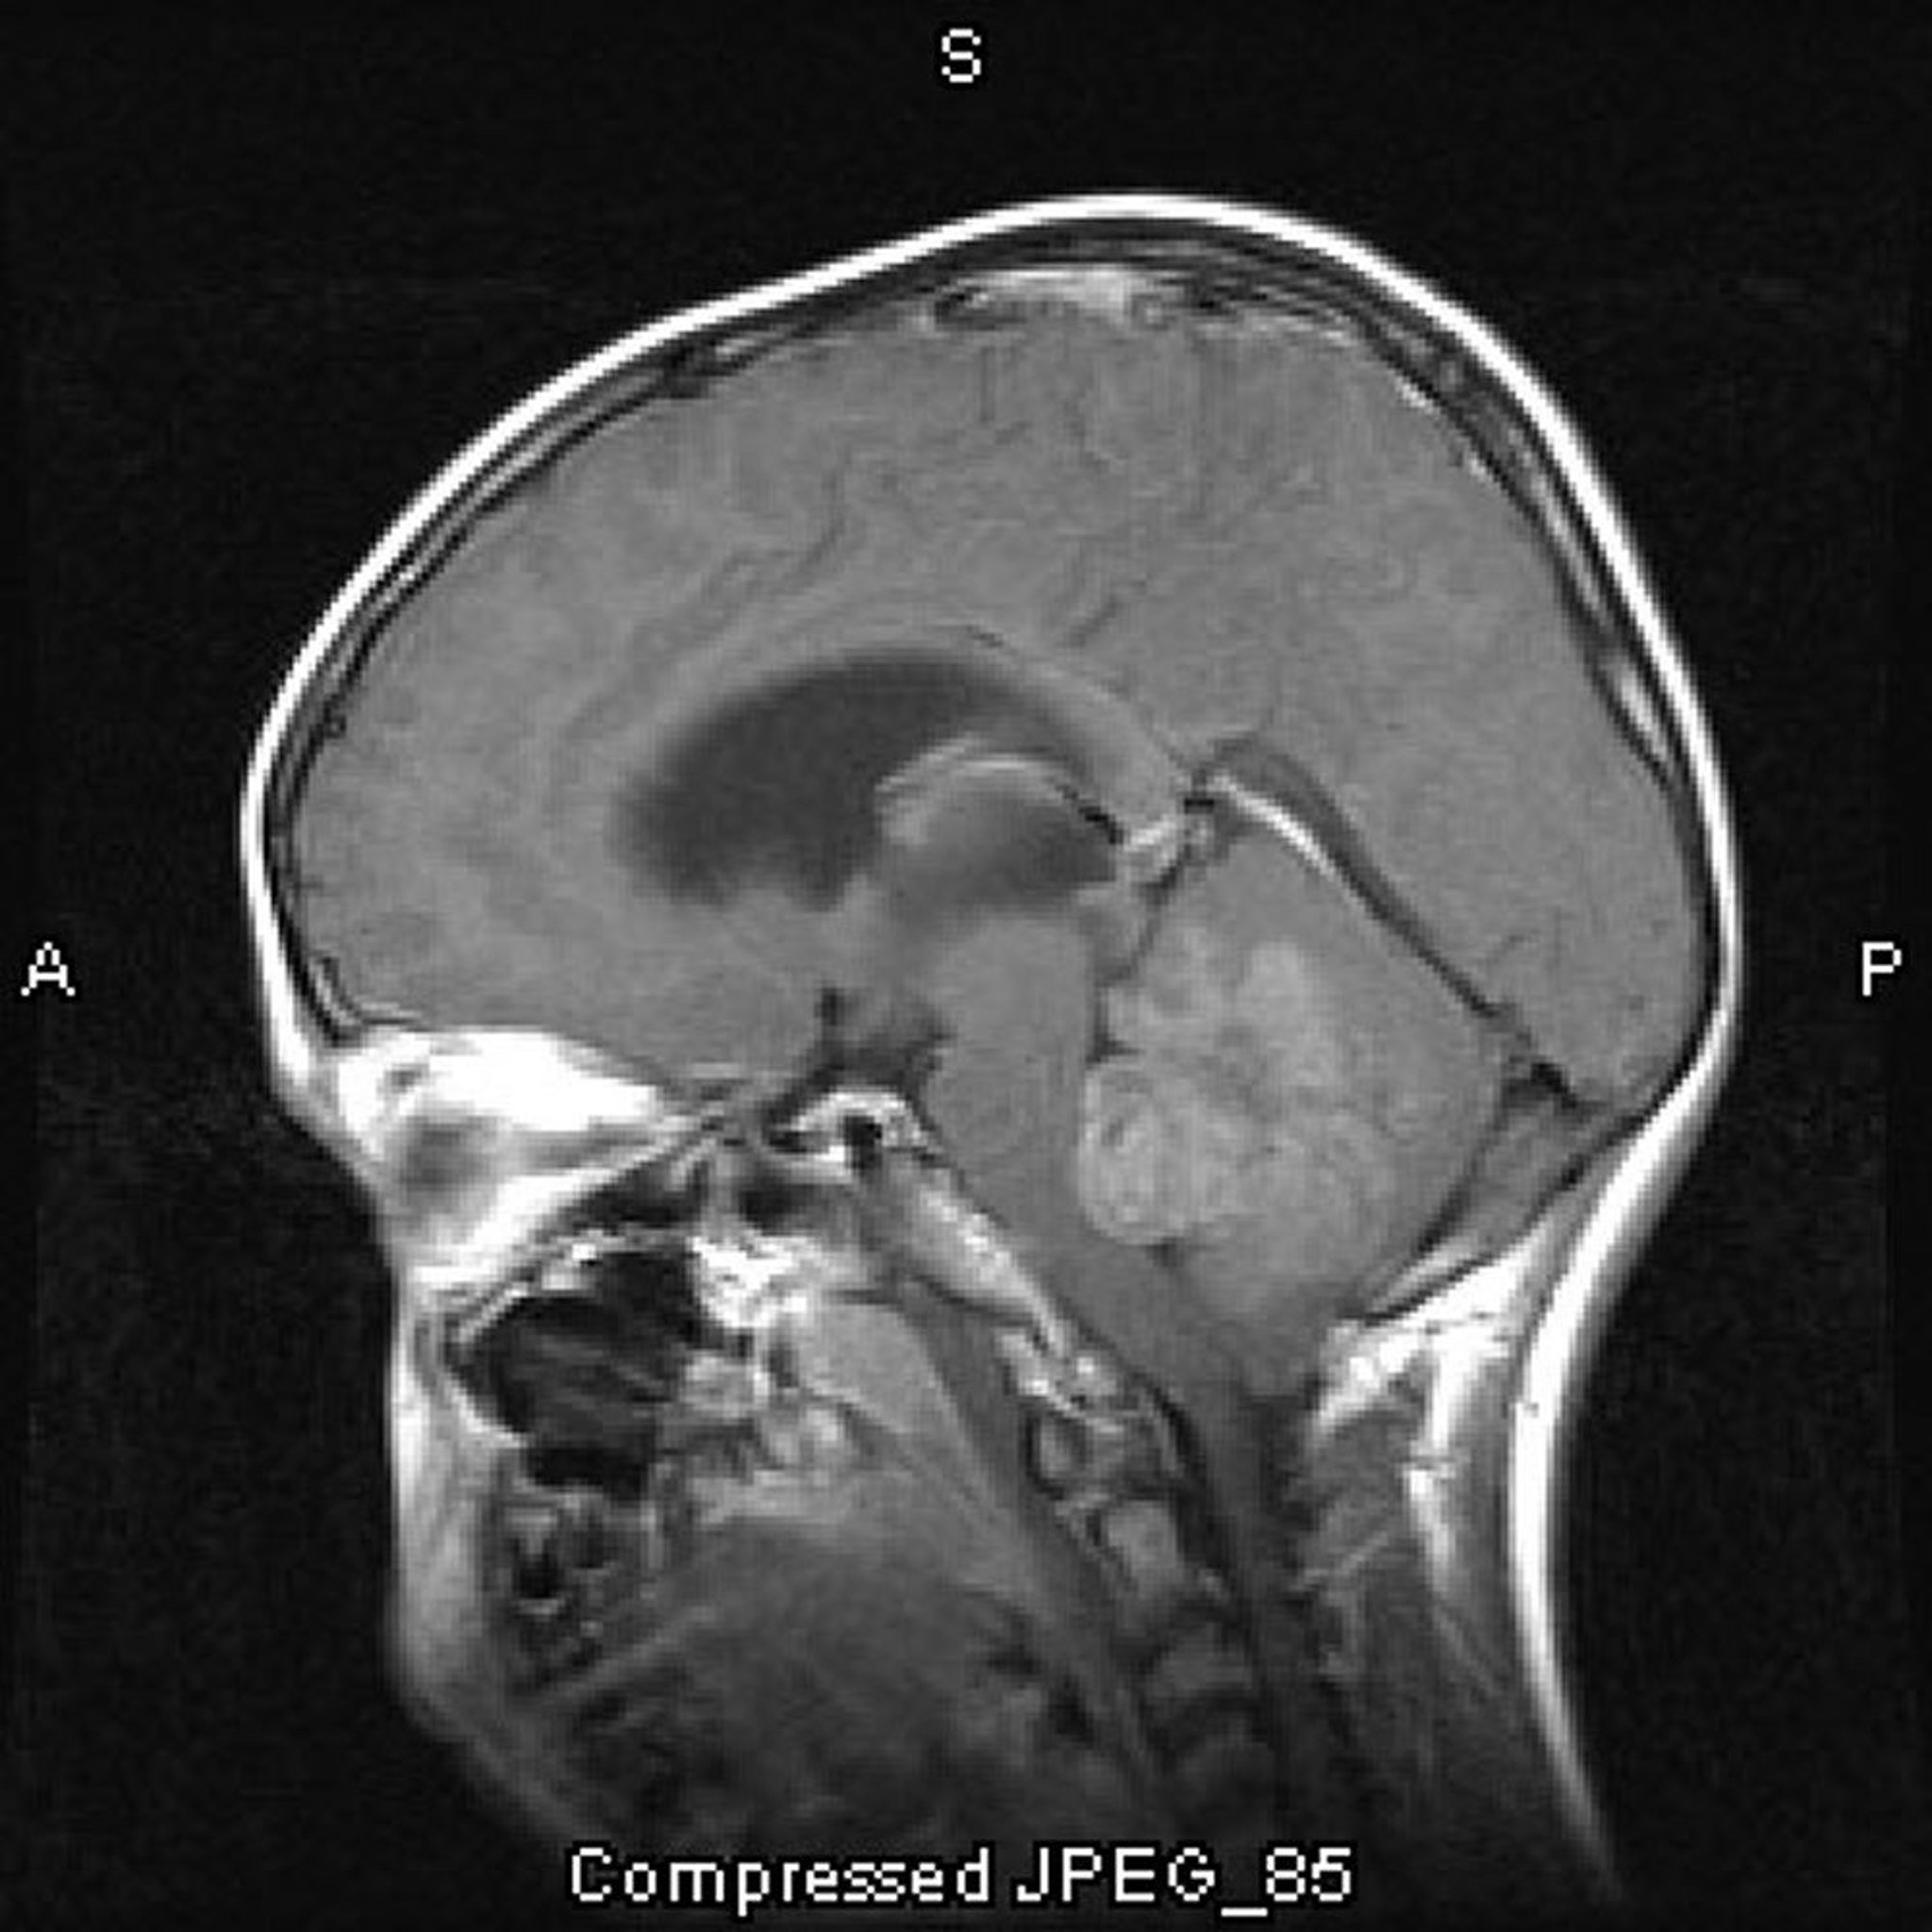

Meduloblastoma

La RM con contraste muestra un meduloblastoma que crece en el interior del cuarto ventrículo y lo obstruye.

Image courtesy of William R. Shapiro, MD.